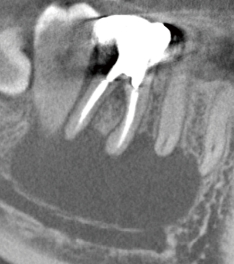

根管長測定

気温や湿度などの環境変化、経年変化によって生じる測定値の誤差を自動で補正し、安定した測定精度を保つオートキャリブレーション機能を搭載。

ドライでもウェットでも根管内の状態に影響されない高精度な測定で治療をサポートします。